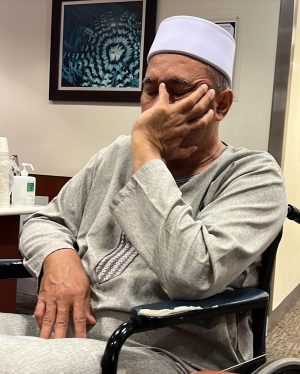

Caption : Kalau anyone you know jatuh kepala terhentak, luaran memang takde apa tapi dalaman maybe boleh jadi pendarahan perlahan. Sejurus dari terjatuh, bila check X-Ray dan CT scan it will tell you nothing, semua clear saja, but 2-3weeks later could turn into your biggest nightmare when the blood has flooded a big part of your brain. My dad realised something was wrong hampir sebulan lepas jatuh, when suddenly he couldn’t really move his right leg. Macam lagging. Sebab dia jatuh terhentak dahi kiri, bila anggota belah kanan yang terjejas, we knew it must be the brain. I picked him up and asked about his very very recent trip to Acheh, he said “Bila Daddy pergi Acheh?”. Ya Allah this very man, is my dad, someone who was very sharp and opinionated, tiba-tiba sangat blur dan slow, jawab sepatah-sepatah. So I spent the whole day uruskan dia, consulted two specialists and one neurosurgeon and when he is finally admitted that night to prepare him for his surgery the following day, he told the family “Daddy tadi drive sendiri datang sini”. My heart sank, I was frantic with worry — takutnya lagi lambat ni lagi banyak memori dia hilang. The brain surgery went well atas izin Allah, thank you to everyone involved. Doktor kata kalau lewat sikit je lagi memang boleh hilang keupayaan bercakap, keupayaan bernafas dan seterusnya koma, sebab otak dah compressed terlalu banyak darah. I jot this here as a reminder for all of us to always jangan tangguh-tangguh kalau hati dah tergerak. Daddy masih tak ingat I bawak dia pi hospital hari tu. Nasib baik kita selfie.Likes : 168141

Caption : Kalau anyone you know jatuh kepala terhentak, luaran memang takde apa tapi dalaman maybe boleh jadi pendarahan perlahan. Sejurus dari terjatuh, bila check X-Ray dan CT scan it will tell you nothing, semua clear saja, but 2-3weeks later could turn into your biggest nightmare when the blood has flooded a big part of your brain. My dad realised something was wrong hampir sebulan lepas jatuh, when suddenly he couldn’t really move his right leg. Macam lagging. Sebab dia jatuh terhentak dahi kiri, bila anggota belah kanan yang terjejas, we knew it must be the brain. I picked him up and asked about his very very recent trip to Acheh, he said “Bila Daddy pergi Acheh?”. Ya Allah this very man, is my dad, someone who was very sharp and opinionated, tiba-tiba sangat blur dan slow, jawab sepatah-sepatah. So I spent the whole day uruskan dia, consulted two specialists and one neurosurgeon and when he is finally admitted that night to prepare him for his surgery the following day, he told the family “Daddy tadi drive sendiri datang sini”. My heart sank, I was frantic with worry — takutnya lagi lambat ni lagi banyak memori dia hilang. The brain surgery went well atas izin Allah, thank you to everyone involved. Doktor kata kalau lewat sikit je lagi memang boleh hilang keupayaan bercakap, keupayaan bernafas dan seterusnya koma, sebab otak dah compressed terlalu banyak darah. I jot this here as a reminder for all of us to always jangan tangguh-tangguh kalau hati dah tergerak. Daddy masih tak ingat I bawak dia pi hospital hari tu. Nasib baik kita selfie.Likes : 168141

Caption : Kalau anyone you know jatuh kepala terhentak, luaran memang takde apa tapi dalaman maybe boleh jadi pendarahan perlahan. Sejurus dari terjatuh, bila check X-Ray dan CT scan it will tell you nothing, semua clear saja, but 2-3weeks later could turn into your biggest nightmare when the blood has flooded a big part of your brain. My dad realised something was wrong hampir sebulan lepas jatuh, when suddenly he couldn’t really move his right leg. Macam lagging. Sebab dia jatuh terhentak dahi kiri, bila anggota belah kanan yang terjejas, we knew it must be the brain. I picked him up and asked about his very very recent trip to Acheh, he said “Bila Daddy pergi Acheh?”. Ya Allah this very man, is my dad, someone who was very sharp and opinionated, tiba-tiba sangat blur dan slow, jawab sepatah-sepatah. So I spent the whole day uruskan dia, consulted two specialists and one neurosurgeon and when he is finally admitted that night to prepare him for his surgery the following day, he told the family “Daddy tadi drive sendiri datang sini”. My heart sank, I was frantic with worry — takutnya lagi lambat ni lagi banyak memori dia hilang. The brain surgery went well atas izin Allah, thank you to everyone involved. Doktor kata kalau lewat sikit je lagi memang boleh hilang keupayaan bercakap, keupayaan bernafas dan seterusnya koma, sebab otak dah compressed terlalu banyak darah. I jot this here as a reminder for all of us to always jangan tangguh-tangguh kalau hati dah tergerak. Daddy masih tak ingat I bawak dia pi hospital hari tu. Nasib baik kita selfie.Likes : 168141

Caption : Kalau anyone you know jatuh kepala terhentak, luaran memang takde apa tapi dalaman maybe boleh jadi pendarahan perlahan. Sejurus dari terjatuh, bila check X-Ray dan CT scan it will tell you nothing, semua clear saja, but 2-3weeks later could turn into your biggest nightmare when the blood has flooded a big part of your brain. My dad realised something was wrong hampir sebulan lepas jatuh, when suddenly he couldn’t really move his right leg. Macam lagging. Sebab dia jatuh terhentak dahi kiri, bila anggota belah kanan yang terjejas, we knew it must be the brain. I picked him up and asked about his very very recent trip to Acheh, he said “Bila Daddy pergi Acheh?”. Ya Allah this very man, is my dad, someone who was very sharp and opinionated, tiba-tiba sangat blur dan slow, jawab sepatah-sepatah. So I spent the whole day uruskan dia, consulted two specialists and one neurosurgeon and when he is finally admitted that night to prepare him for his surgery the following day, he told the family “Daddy tadi drive sendiri datang sini”. My heart sank, I was frantic with worry — takutnya lagi lambat ni lagi banyak memori dia hilang. The brain surgery went well atas izin Allah, thank you to everyone involved. Doktor kata kalau lewat sikit je lagi memang boleh hilang keupayaan bercakap, keupayaan bernafas dan seterusnya koma, sebab otak dah compressed terlalu banyak darah. I jot this here as a reminder for all of us to always jangan tangguh-tangguh kalau hati dah tergerak. Daddy masih tak ingat I bawak dia pi hospital hari tu. Nasib baik kita selfie.Likes : 168141

Caption : Kalau anyone you know jatuh kepala terhentak, luaran memang takde apa tapi dalaman maybe boleh jadi pendarahan perlahan. Sejurus dari terjatuh, bila check X-Ray dan CT scan it will tell you nothing, semua clear saja, but 2-3weeks later could turn into your biggest nightmare when the blood has flooded a big part of your brain. My dad realised something was wrong hampir sebulan lepas jatuh, when suddenly he couldn’t really move his right leg. Macam lagging. Sebab dia jatuh terhentak dahi kiri, bila anggota belah kanan yang terjejas, we knew it must be the brain. I picked him up and asked about his very very recent trip to Acheh, he said “Bila Daddy pergi Acheh?”. Ya Allah this very man, is my dad, someone who was very sharp and opinionated, tiba-tiba sangat blur dan slow, jawab sepatah-sepatah. So I spent the whole day uruskan dia, consulted two specialists and one neurosurgeon and when he is finally admitted that night to prepare him for his surgery the following day, he told the family “Daddy tadi drive sendiri datang sini”. My heart sank, I was frantic with worry — takutnya lagi lambat ni lagi banyak memori dia hilang. The brain surgery went well atas izin Allah, thank you to everyone involved. Doktor kata kalau lewat sikit je lagi memang boleh hilang keupayaan bercakap, keupayaan bernafas dan seterusnya koma, sebab otak dah compressed terlalu banyak darah. I jot this here as a reminder for all of us to always jangan tangguh-tangguh kalau hati dah tergerak. Daddy masih tak ingat I bawak dia pi hospital hari tu. Nasib baik kita selfie.Likes : 168141

Caption : Kalau anyone you know jatuh kepala terhentak, luaran memang takde apa tapi dalaman maybe boleh jadi pendarahan perlahan. Sejurus dari terjatuh, bila check X-Ray dan CT scan it will tell you nothing, semua clear saja, but 2-3weeks later could turn into your biggest nightmare when the blood has flooded a big part of your brain. My dad realised something was wrong hampir sebulan lepas jatuh, when suddenly he couldn’t really move his right leg. Macam lagging. Sebab dia jatuh terhentak dahi kiri, bila anggota belah kanan yang terjejas, we knew it must be the brain. I picked him up and asked about his very very recent trip to Acheh, he said “Bila Daddy pergi Acheh?”. Ya Allah this very man, is my dad, someone who was very sharp and opinionated, tiba-tiba sangat blur dan slow, jawab sepatah-sepatah. So I spent the whole day uruskan dia, consulted two specialists and one neurosurgeon and when he is finally admitted that night to prepare him for his surgery the following day, he told the family “Daddy tadi drive sendiri datang sini”. My heart sank, I was frantic with worry — takutnya lagi lambat ni lagi banyak memori dia hilang. The brain surgery went well atas izin Allah, thank you to everyone involved. Doktor kata kalau lewat sikit je lagi memang boleh hilang keupayaan bercakap, keupayaan bernafas dan seterusnya koma, sebab otak dah compressed terlalu banyak darah. I jot this here as a reminder for all of us to always jangan tangguh-tangguh kalau hati dah tergerak. Daddy masih tak ingat I bawak dia pi hospital hari tu. Nasib baik kita selfie.Likes : 168141

Caption : Kalau anyone you know jatuh kepala terhentak, luaran memang takde apa tapi dalaman maybe boleh jadi pendarahan perlahan. Sejurus dari terjatuh, bila check X-Ray dan CT scan it will tell you nothing, semua clear saja, but 2-3weeks later could turn into your biggest nightmare when the blood has flooded a big part of your brain. My dad realised something was wrong hampir sebulan lepas jatuh, when suddenly he couldn’t really move his right leg. Macam lagging. Sebab dia jatuh terhentak dahi kiri, bila anggota belah kanan yang terjejas, we knew it must be the brain. I picked him up and asked about his very very recent trip to Acheh, he said “Bila Daddy pergi Acheh?”. Ya Allah this very man, is my dad, someone who was very sharp and opinionated, tiba-tiba sangat blur dan slow, jawab sepatah-sepatah. So I spent the whole day uruskan dia, consulted two specialists and one neurosurgeon and when he is finally admitted that night to prepare him for his surgery the following day, he told the family “Daddy tadi drive sendiri datang sini”. My heart sank, I was frantic with worry — takutnya lagi lambat ni lagi banyak memori dia hilang. The brain surgery went well atas izin Allah, thank you to everyone involved. Doktor kata kalau lewat sikit je lagi memang boleh hilang keupayaan bercakap, keupayaan bernafas dan seterusnya koma, sebab otak dah compressed terlalu banyak darah. I jot this here as a reminder for all of us to always jangan tangguh-tangguh kalau hati dah tergerak. Daddy masih tak ingat I bawak dia pi hospital hari tu. Nasib baik kita selfie.Likes : 168141

Caption : Kalau anyone you know jatuh kepala terhentak, luaran memang takde apa tapi dalaman maybe boleh jadi pendarahan perlahan. Sejurus dari terjatuh, bila check X-Ray dan CT scan it will tell you nothing, semua clear saja, but 2-3weeks later could turn into your biggest nightmare when the blood has flooded a big part of your brain. My dad realised something was wrong hampir sebulan lepas jatuh, when suddenly he couldn’t really move his right leg. Macam lagging. Sebab dia jatuh terhentak dahi kiri, bila anggota belah kanan yang terjejas, we knew it must be the brain. I picked him up and asked about his very very recent trip to Acheh, he said “Bila Daddy pergi Acheh?”. Ya Allah this very man, is my dad, someone who was very sharp and opinionated, tiba-tiba sangat blur dan slow, jawab sepatah-sepatah. So I spent the whole day uruskan dia, consulted two specialists and one neurosurgeon and when he is finally admitted that night to prepare him for his surgery the following day, he told the family “Daddy tadi drive sendiri datang sini”. My heart sank, I was frantic with worry — takutnya lagi lambat ni lagi banyak memori dia hilang. The brain surgery went well atas izin Allah, thank you to everyone involved. Doktor kata kalau lewat sikit je lagi memang boleh hilang keupayaan bercakap, keupayaan bernafas dan seterusnya koma, sebab otak dah compressed terlalu banyak darah. I jot this here as a reminder for all of us to always jangan tangguh-tangguh kalau hati dah tergerak. Daddy masih tak ingat I bawak dia pi hospital hari tu. Nasib baik kita selfie.Likes : 168141

Caption : Kalau anyone you know jatuh kepala terhentak, luaran memang takde apa tapi dalaman maybe boleh jadi pendarahan perlahan. Sejurus dari terjatuh, bila check X-Ray dan CT scan it will tell you nothing, semua clear saja, but 2-3weeks later could turn into your biggest nightmare when the blood has flooded a big part of your brain. My dad realised something was wrong hampir sebulan lepas jatuh, when suddenly he couldn’t really move his right leg. Macam lagging. Sebab dia jatuh terhentak dahi kiri, bila anggota belah kanan yang terjejas, we knew it must be the brain. I picked him up and asked about his very very recent trip to Acheh, he said “Bila Daddy pergi Acheh?”. Ya Allah this very man, is my dad, someone who was very sharp and opinionated, tiba-tiba sangat blur dan slow, jawab sepatah-sepatah. So I spent the whole day uruskan dia, consulted two specialists and one neurosurgeon and when he is finally admitted that night to prepare him for his surgery the following day, he told the family “Daddy tadi drive sendiri datang sini”. My heart sank, I was frantic with worry — takutnya lagi lambat ni lagi banyak memori dia hilang. The brain surgery went well atas izin Allah, thank you to everyone involved. Doktor kata kalau lewat sikit je lagi memang boleh hilang keupayaan bercakap, keupayaan bernafas dan seterusnya koma, sebab otak dah compressed terlalu banyak darah. I jot this here as a reminder for all of us to always jangan tangguh-tangguh kalau hati dah tergerak. Daddy masih tak ingat I bawak dia pi hospital hari tu. Nasib baik kita selfie.Likes : 168141

Caption : Kalau anyone you know jatuh kepala terhentak, luaran memang takde apa tapi dalaman maybe boleh jadi pendarahan perlahan. Sejurus dari terjatuh, bila check X-Ray dan CT scan it will tell you nothing, semua clear saja, but 2-3weeks later could turn into your biggest nightmare when the blood has flooded a big part of your brain. My dad realised something was wrong hampir sebulan lepas jatuh, when suddenly he couldn’t really move his right leg. Macam lagging. Sebab dia jatuh terhentak dahi kiri, bila anggota belah kanan yang terjejas, we knew it must be the brain. I picked him up and asked about his very very recent trip to Acheh, he said “Bila Daddy pergi Acheh?”. Ya Allah this very man, is my dad, someone who was very sharp and opinionated, tiba-tiba sangat blur dan slow, jawab sepatah-sepatah. So I spent the whole day uruskan dia, consulted two specialists and one neurosurgeon and when he is finally admitted that night to prepare him for his surgery the following day, he told the family “Daddy tadi drive sendiri datang sini”. My heart sank, I was frantic with worry — takutnya lagi lambat ni lagi banyak memori dia hilang. The brain surgery went well atas izin Allah, thank you to everyone involved. Doktor kata kalau lewat sikit je lagi memang boleh hilang keupayaan bercakap, keupayaan bernafas dan seterusnya koma, sebab otak dah compressed terlalu banyak darah. I jot this here as a reminder for all of us to always jangan tangguh-tangguh kalau hati dah tergerak. Daddy masih tak ingat I bawak dia pi hospital hari tu. Nasib baik kita selfie.Likes : 168141